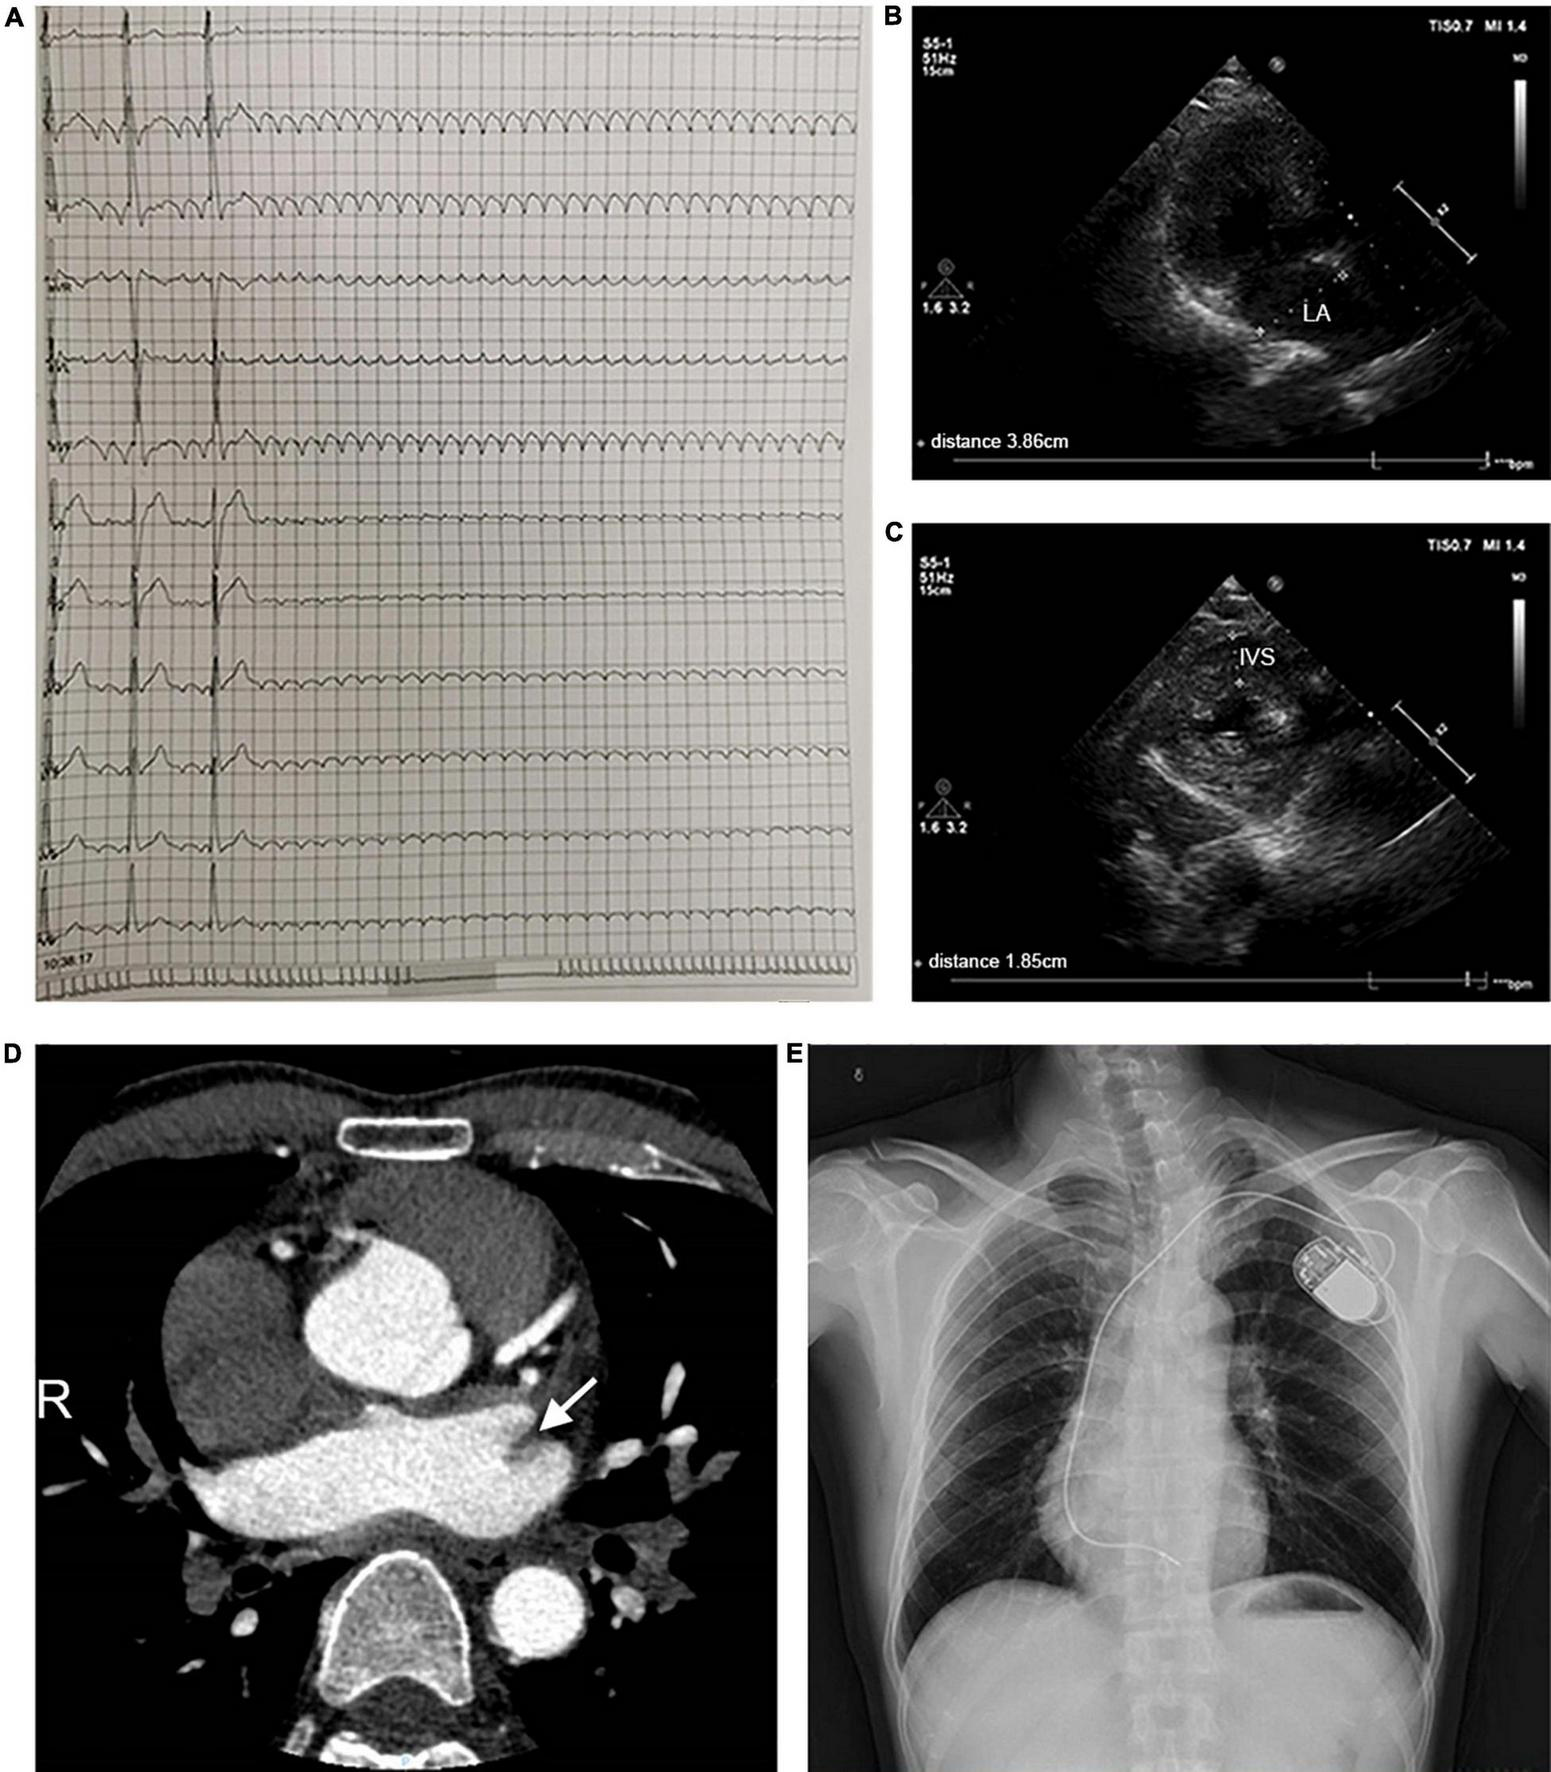

A 44-year-old patient from a family with suspected inherited cardiomyopathy was hospitalized for the presentation of palpitations and syncope. Atrial flutter and intermittent high-grade AV block (the longest RR was 11.275 s) were observed under 24-h Holter-ECG monitoring (Figure 1A). An electrocardiogram (ECG) of the proband simultaneously revealed typical atrial flutter (Supplementary Figure 1A). Echocardiography demonstrated that the proband’s atrium was enlarged [left atrium diameter (LAD): 39 mm (Figure 1B); right atrium diameter (RAD): 38 mm], whereas both the ejection fraction (EF) and left ventricular end-diastolic diameter (LVDd) were normal (Supplementary Table 1). The proband’s interventricular septum was hypertrophic (IVS: 18 mm, Figure 1C), but neither ST-segment change nor T-wave inversion was observed in the ECG. Considering that left atrial hemodynamics can be altered by atrial flutter, the left atrial appendage (LAA) was analyzed in detail using enhanced cardiac CT scans. The results indicated the presence of an LAA thrombus (Figure 1D). Considering the proband’s diseases and probable thrombus formation, radiofrequency ablation of atrial flutter was terminated. A permanent pacemaker was implanted instead. After implantation, a posteroanterior chest X-ray showed no evident abnormality in the size and shape of the ventricle (Figure 1E).

Clinical parameters for the pedigree. (A) 24-h Holter monitoring of the proband. (B,C) Echocardiographic parameters, including LAD and IVS. (D) The cardiac CT-scan indicated atrial thrombus (shown by the arrow). (E) A posteroanterior chest X-ray was taken immediately after pacemaker implantation. Abbreviations: LA, left atrium; IVS, interventricular septum.